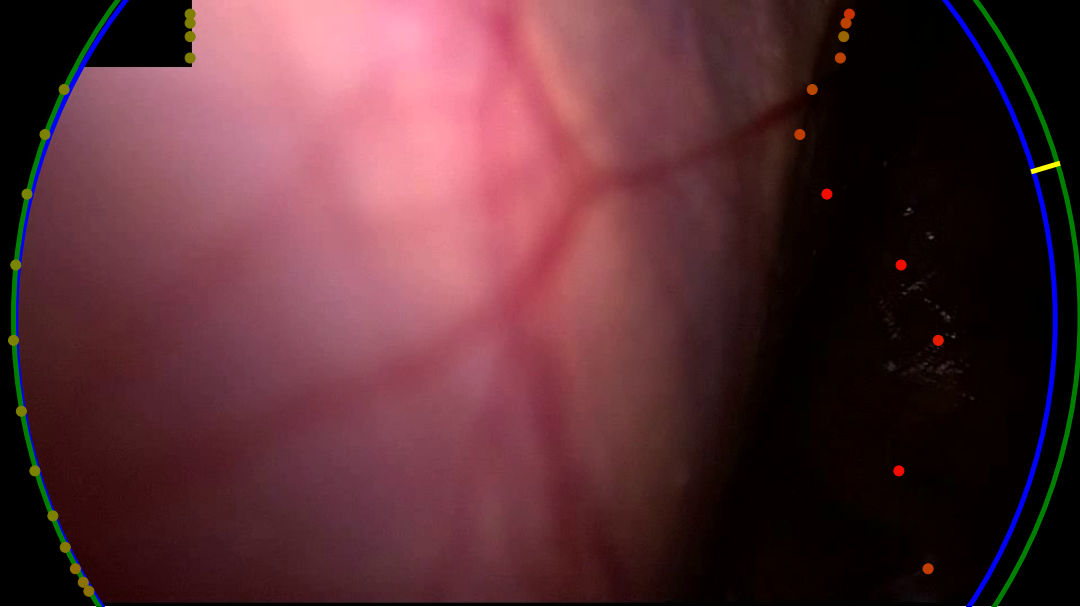

Refer to caption

(a) The dark right-hand side of the content area is missed by both variants. The learned variant gets a slightly better fit, this could be due to a better positioing of points on the left-hand side of the content area.

(b) A noisy and bright border poses a challenge for the handcrafted variant. Too few edge points are detected to make a confident estimate of the circle. The learned variant manages to correctly identify the right-hand edge of the content area, however, the circle fits to incorrect edge points found on the blacked out secondary video feed in the top-left.

(c) Both variants correctly identify the edge in the bottom-left but mistake dark regions in the top-right and bottom-right corners as border regions. The learned variant rejects the final circle as the circle score is too low. This scenario, where a single corner of the image is outside the content area, features prominantly in our failure cases.

(d) In this sample, the handcrafted variant detects edge points in the bottom-left, but scores them poorly. The circle fitting then chooses the incorrectly identified edge points in the top-left. The learned variant scores the detected points in the bottom-left higher, and so the circle fitting finds a satisfying result.

Figure 6: A selection of failure cases of our algorithm taken from the RobustECA dataset, the results of both the handcrafted (left) and learned (right) variants are shown for each image. The edge of the ground truth and inferred circular image projections are shown in blue, and green, respectively. Points indicate the position of detected edge points, the colour of each point indicates its score, going from red to green as the score increases. The vector found when calculating the Hausdorff distance is shown in yellow.